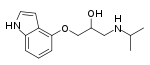

Propanolamines are a class of chemical compounds, many of which are pharmaceutical drugs. They are amino alcohols that are derivatives of 1-amino-2-propanol.[1]

Propanolamines include: